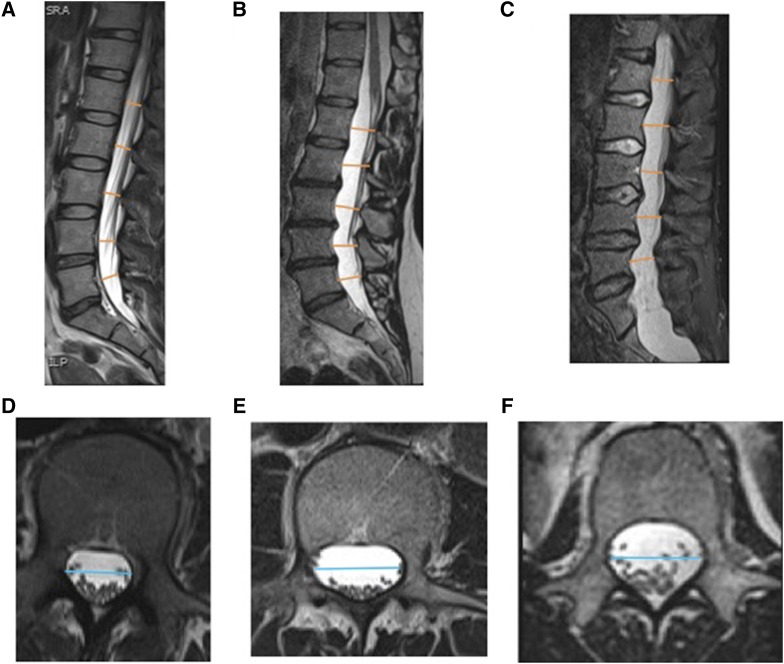

We saw similar results for L1–L5 (average) TR-DSD measurements (Figure 2). The measurement in the idiopathic bronchiectasis group (2.02 ± 0.24 cm) was significantly larger than those in the control (1.89 ± 0.17 cm) and cystic fibrosis groups (1.78 ± 0.19 cm) (P < 0.001). The L1–L5 (average) TR-DSD of the Marfan syndrome group (2.22 ± 0.32 cm) was larger than that in the L1–L5 (average) TR-DSD of the idiopathic bronchiectasis group (P = 0.001). Sagittal and axial MR images of the dural sac in a representative patient with idiopathic bronchiectasis are compared in Figure 3 with images obtained from a healthy control subject and a patient with Marfan syndrome.

Figure 3.

Sagittal (A–C) and axial (D–F) T2-weighted three-dimensional turbo spin-echo magnetic resonance images of the lumbosacral spine. Axial images are at the L2 vertebral level. Measurement locations of anterior–posterior dural sac diameter (AP-DSD) (orange lines) and transverse dural sac diameter (TR-DSD) (blue lines) of a healthy control subject (A, D), of a subject with idiopathic bronchiectasis (B, E), and of a patient with Marfan syndrome (C, F).